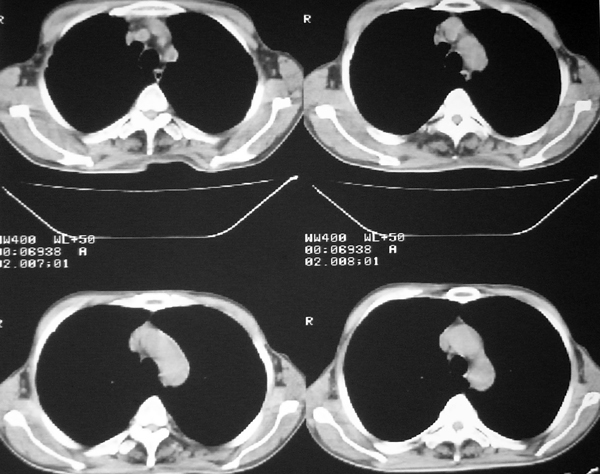

我认为本例肿块内为坏死组织与实性组织混在一起,并夹杂有极低密度气体影,加上肺肿边缘部分呈不规则浅分叶,应该诊断为周围型肺癌。

患者三个月前的ct增强片也显示肿块壁不规则并有明确的壁结节,也支持周围型肺癌的诊断。

如果患者仅是单纯的慢性肺脓疡,在经历了三个多月的治疗后,其内的坏死液化组织与气体应该形形一些短的气-液平面,而本例肿块内没有一个典型的气-液平面。

感谢楼主反馈结果。囊实性肿块,壁厚薄不均,壁结节有明显强化,均支持肺癌诊断。